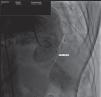

The diagnostic investigation, including computed tomography (CT) angiography (Figure 1) and left ventricular angiography (Figure 2), showed a large (52 mm×48 mm×55 mm) left ventricular wall pseudoaneurysm and a 21 mm×24 mm defect in the ventricular wall.

Figure 1.

Computed tomography angiography showing a large left ventricular wall pseudoaneurysm with a defect in the ventricular wall.